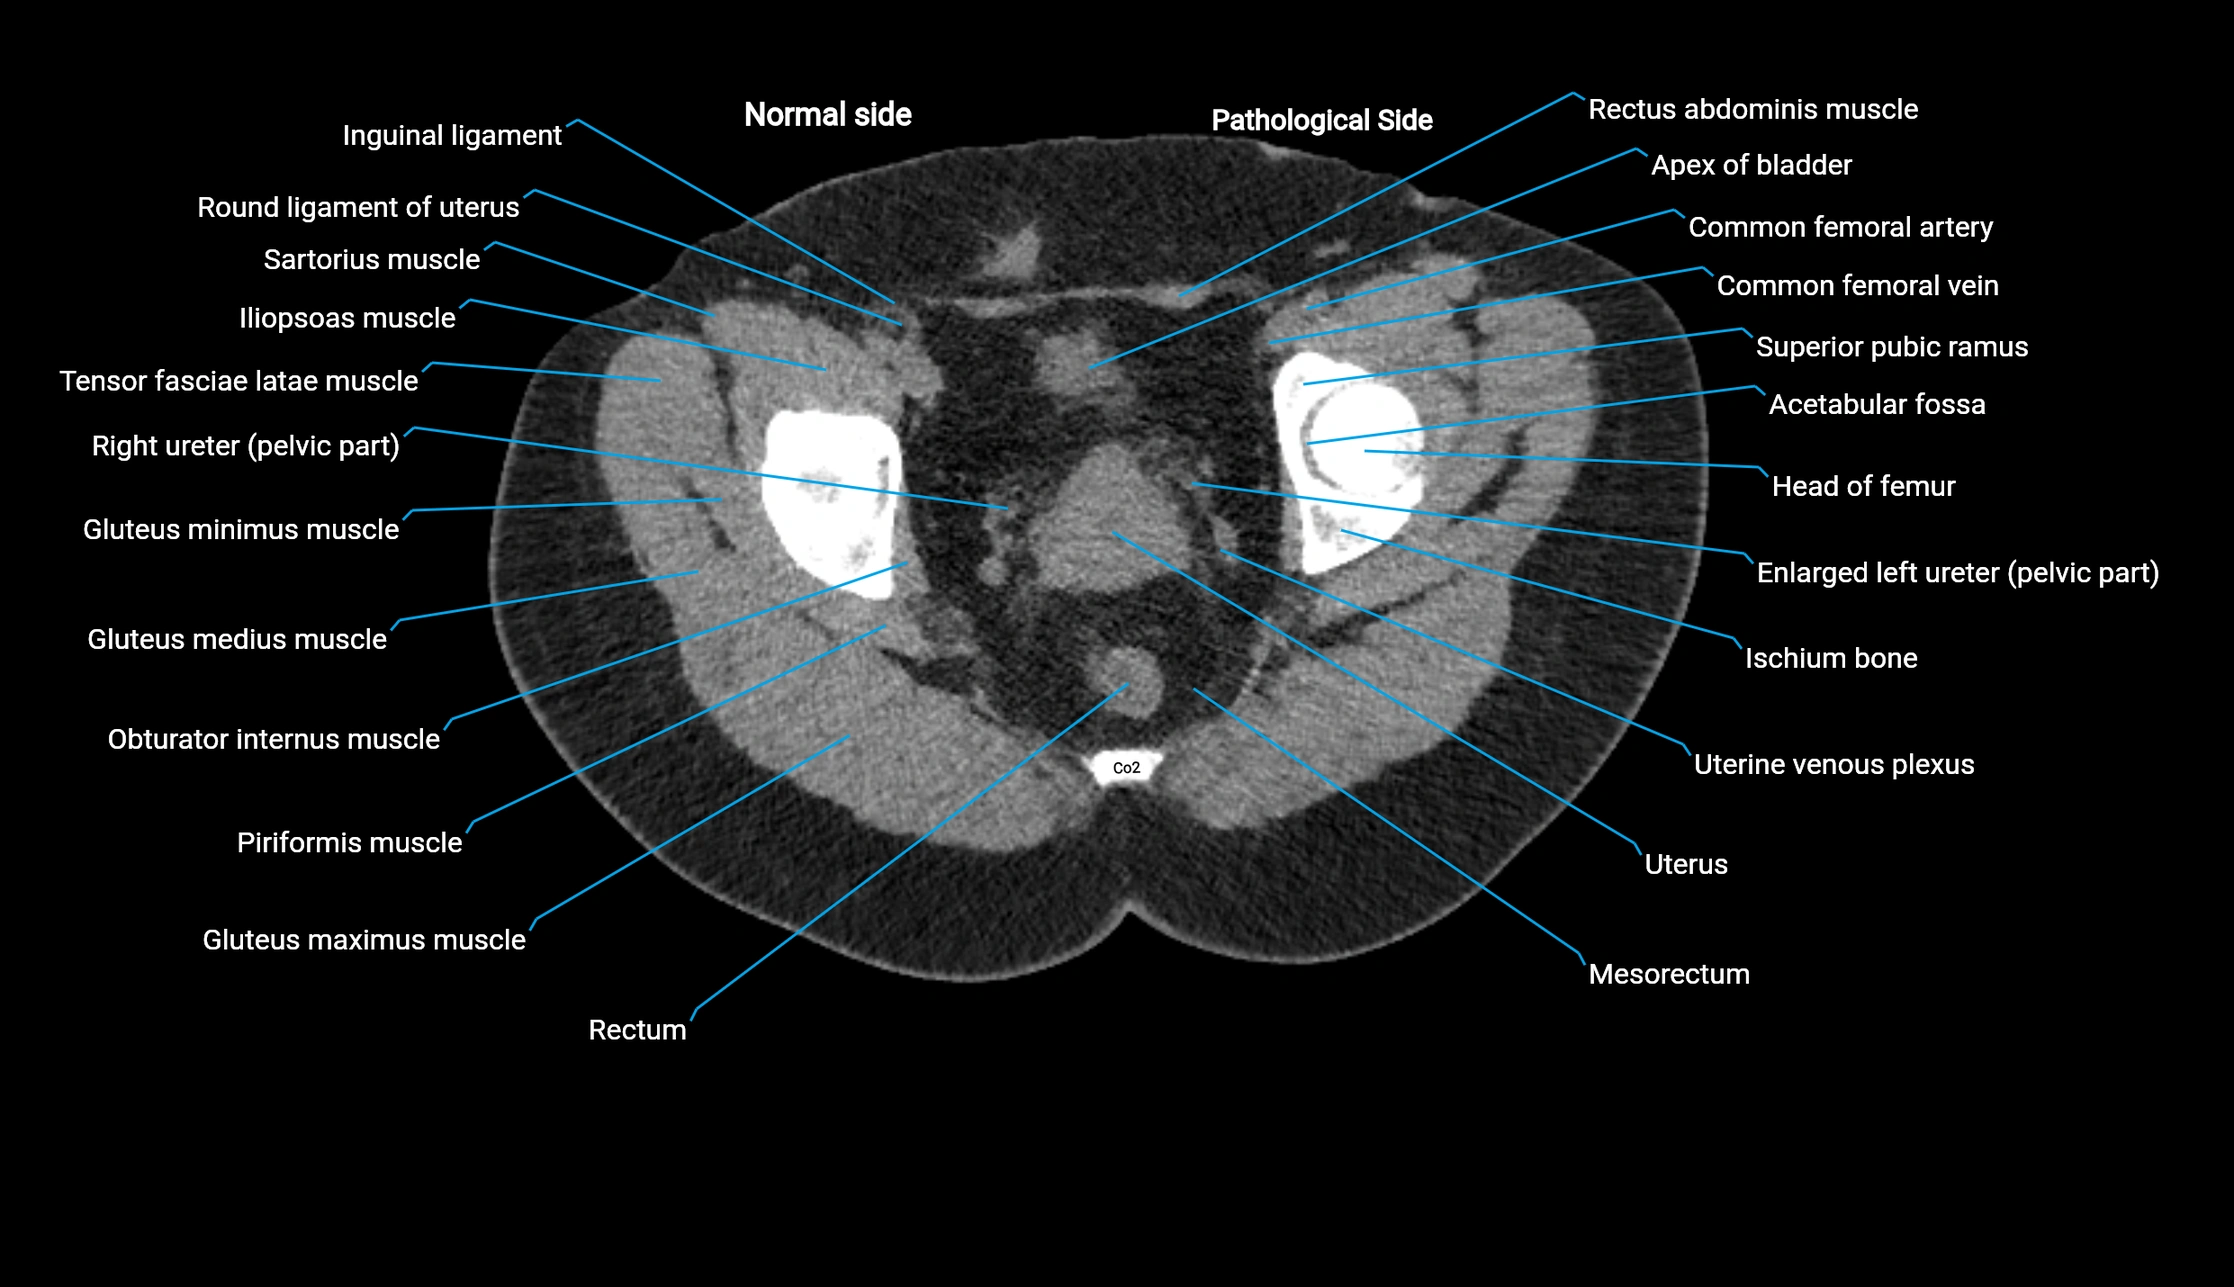

CT image

image